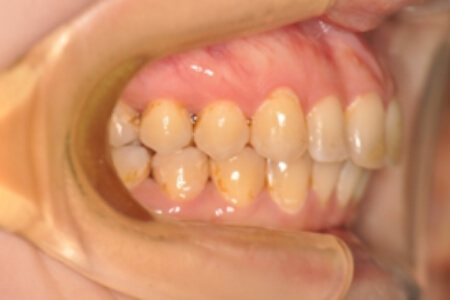

初診時

症例 症例 症例 症例

年齢

30歳 性 別 女性

治療期間 2年11か月 費 用 矯正施術料:1,000,000円

調整料:4,000円/月

治療内容の詳細 初診時30歳の女性で、全体的ながたつきを主訴として来院されました。

検査の結果、過蓋咬合を伴う、アングルⅡ級1類不正咬合と診断しました。

治療としては、非抜歯の上、セルフライゲーションブラケット装置(デーモンシステム)とマウスピース矯正装置(インビザライン)で歯の配列を行いました。

同時に顎間ゴムにて咬合関係の改善を行いました。

治療期間は2年11か月でした。